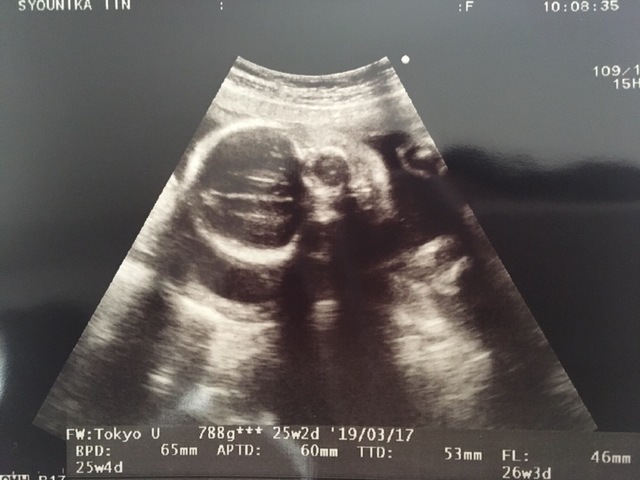

25週2日(25w2d・男の子)|May33 さん(29歳)

エコー写真撮影時のエピソード:

はじめて顔のパーツがはっきりワカルヨウナ正面からのエコー写真が撮れてとても嬉しくて、すぐに旦那さんにLINEで送りました。みんなからは目が大きいんじゃない?と言われてとても嬉しかったです。この頃は胎動がハッキリと分かるようになってきて、お腹も膨らんでいたので赤ちゃんが居ることを実感できるのが嬉しかったです。